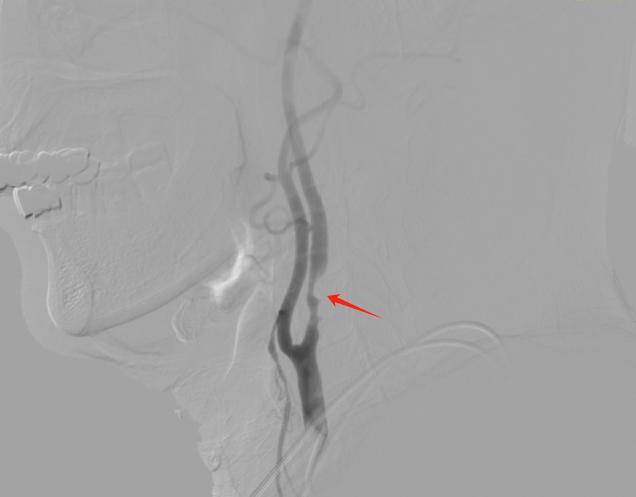

△术前DSA检查,红箭头所示为血管狭窄处

怀着强烈的担忧,李爷爷专程前往省二医院脑血管神经外科就诊。刘坤主任团队接诊后,为其进行了全面细致的术前评估,结合患者年龄、基础病史及血管狭窄情况,最终确定为其实施颈动脉内膜剥脱术。手术过程十分顺利,医生精准剥离出堵塞血管的巨大粥样硬化斑块,成功恢复了脑部供血通道,也驱散了长期笼罩在患者及家属心头的焦虑。